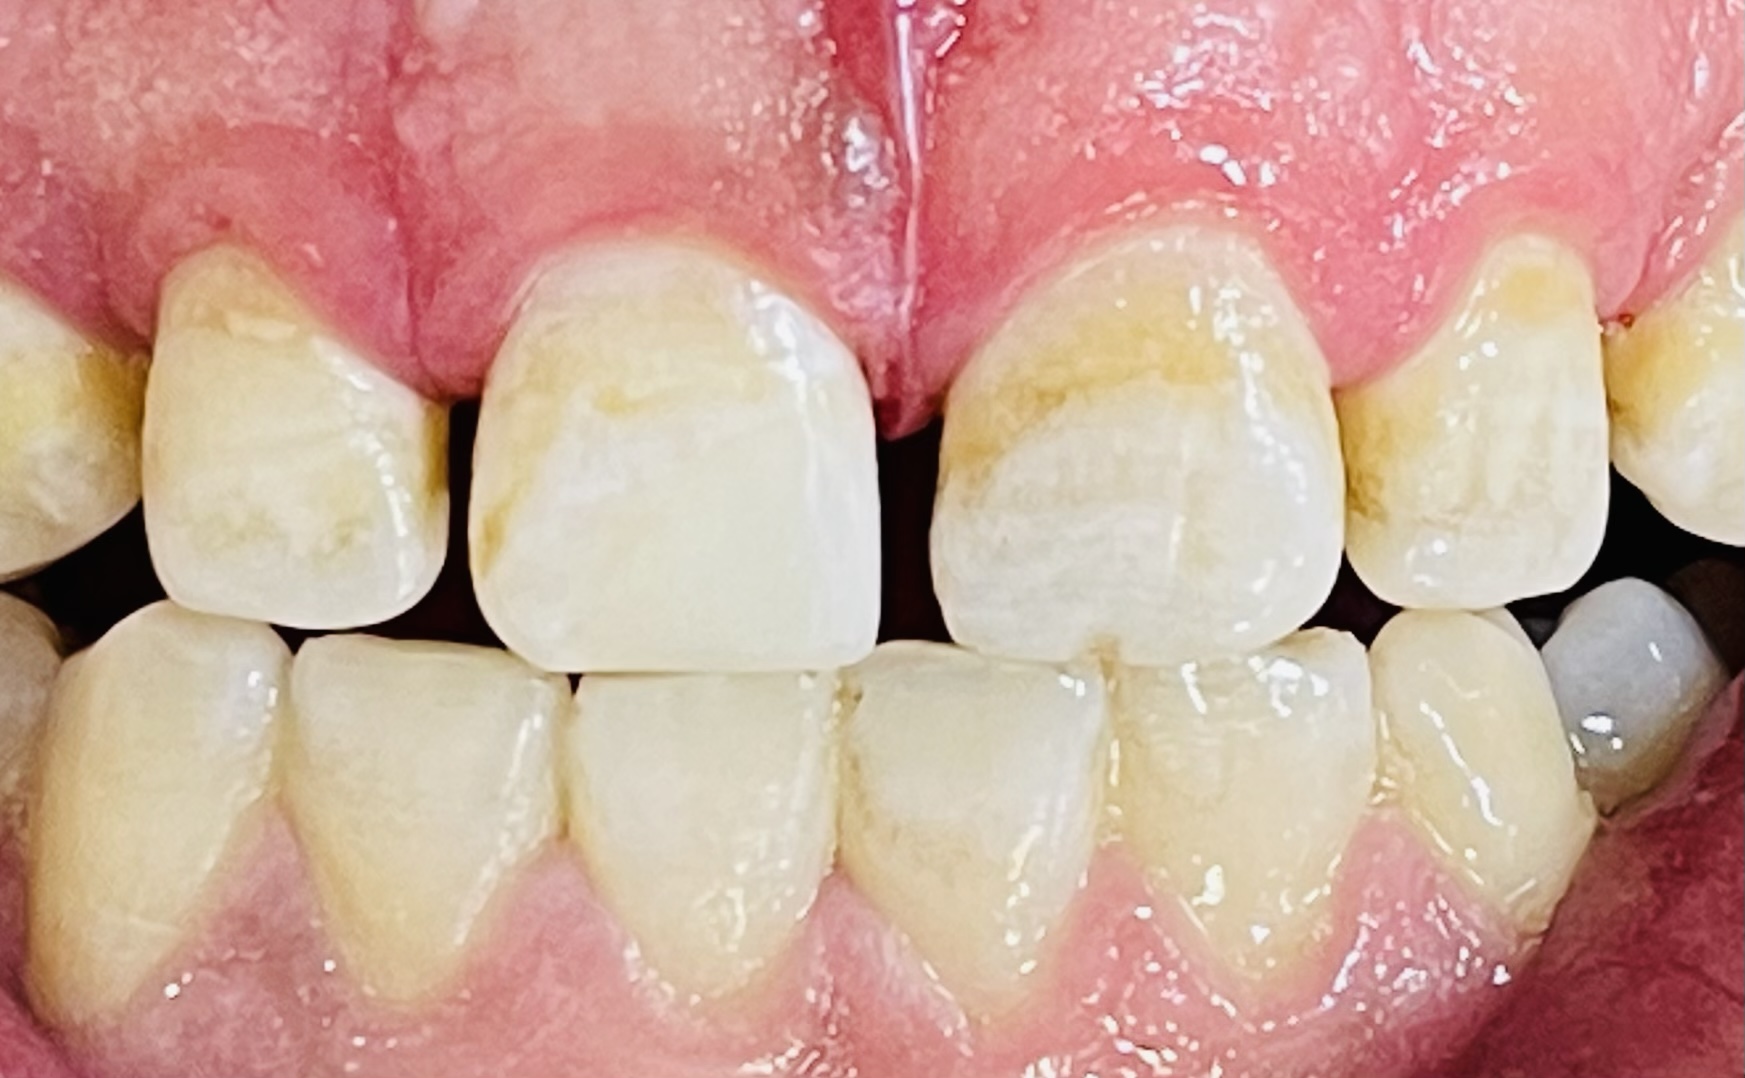

أجراء حشوات امامية مميزة في عيادة معالجة الأسنان